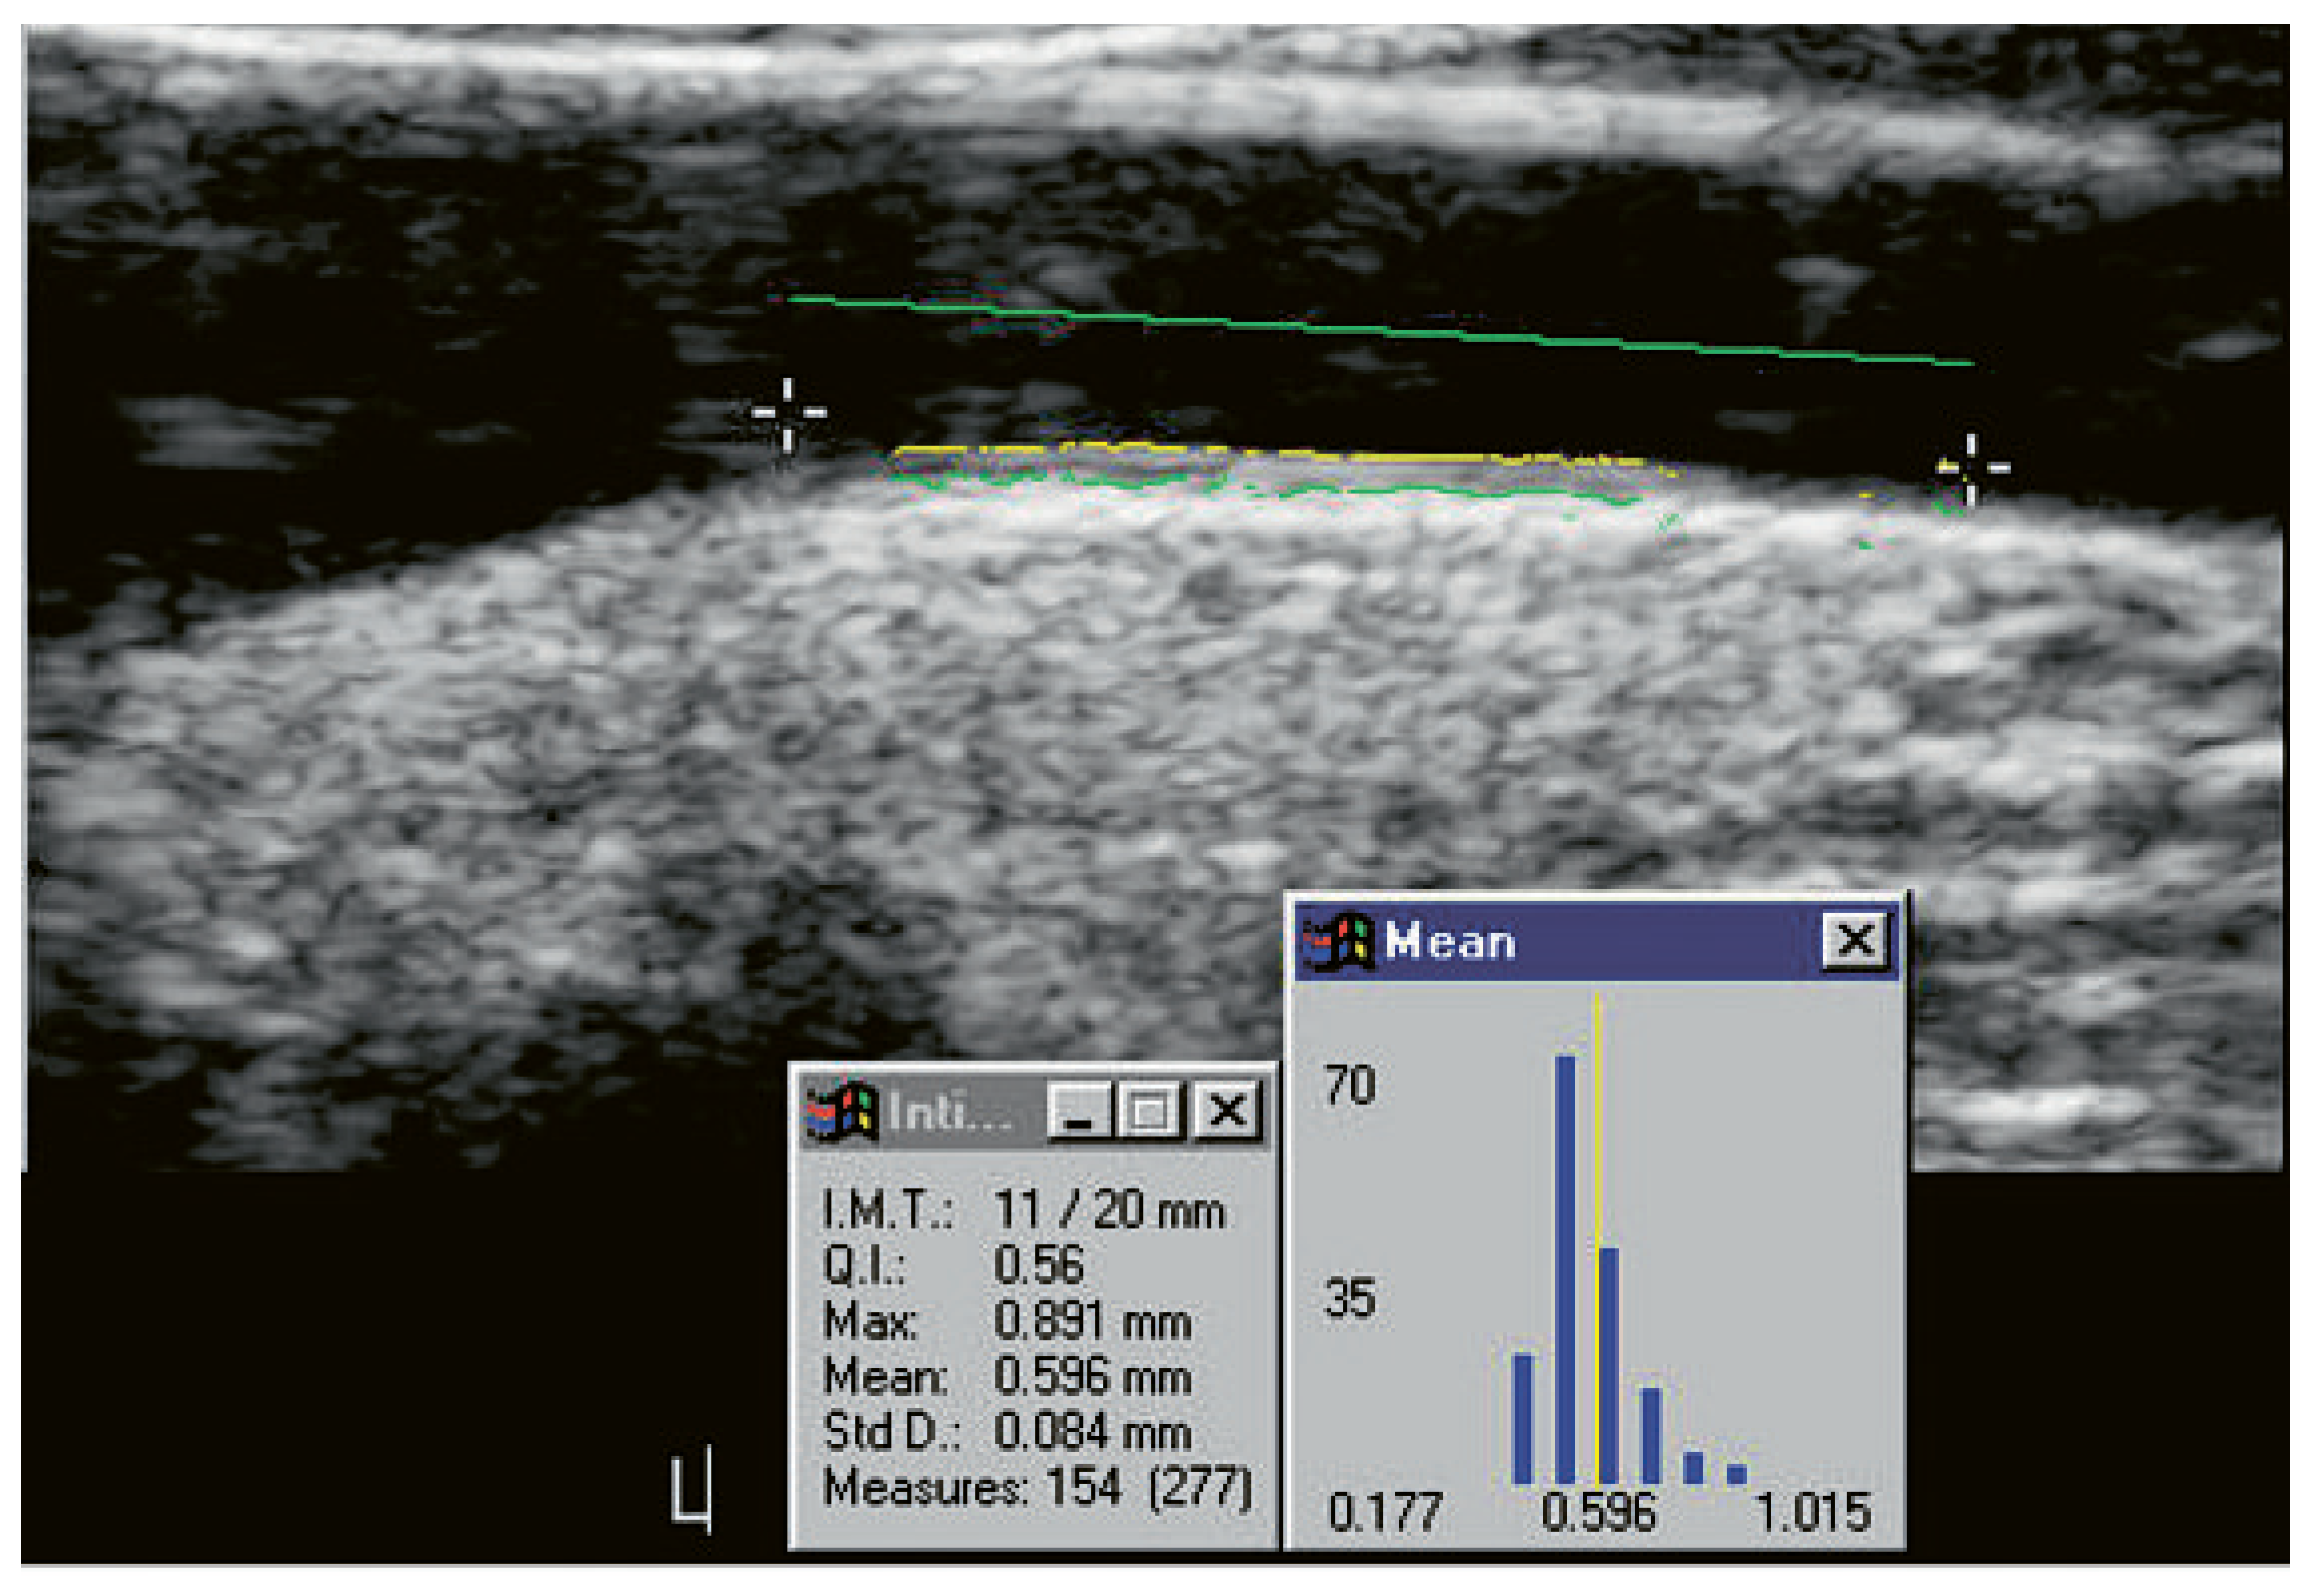

Further, by using only high resolution B-mode ultrasound transducers (≥10 mHz), better results in cardiovascular risk prediction may be achieved. For intervention studies, carotid IMT should be measured in a standardised manner as defined by the European consensus paper [12], preferably at the common carotid artery far wall. Further, although manual tracing is feasible and reproducible, semi-automatic software, as exemplified in Figure 1, is readily performed and easy to handle.

Figure 1. Carotid IMT. The figure shows a case of IMT quantification with the M’ATH software. The mean common carotid IMT was 0.60 mm.